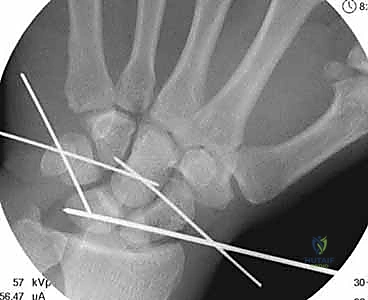

Surgeon: "Once the lunate is reduced, we need to confirm our reduction with fluoroscopy. Assistant, please bring in the C-arm for true PA and lateral views. We're looking for the restoration of Gilula's lines on PA, and the concentricity of the 'C's' (distal radius, lunate, capitate) on the lateral view. The scapholunate angle should be between 40 to 60 degrees, and both the capitolunate and radiolunate angles should be less than 15 degrees. These are our radiographic benchmarks for an anatomical reduction."

Surgeon: "With the carpus reduced, we'll now insert additional transfixation pins percutaneously. These pins will stabilize the scaphoid and triquetrum to the capitate, providing crucial temporary stability to the midcarpal joint."

Figure 3A: Transfixation pins are percutaneously introduced to stabilize the scaphoid and triquetrum to the capitate.

Surgeon: "Now, let's address any associated carpal fractures. The most common is a scaphoid fracture, usually at its waist or proximal pole. For a non-comminuted fracture, we'll use a cannulated headless compression screw. We'll approach this with an antegrade technique, from proximal to distal, ensuring precise alignment under fluoroscopic guidance. For comminuted fractures, we'll apply autologous cancellous bone graft to the fracture site before final tightening of the screw. Fluoroscopy is absolutely essential here for accurate alignment and screw placement, preventing malunion or nonunion."

Surgeon: "Once the fractures are fixed and the carpus is reduced and temporarily stabilized with K-wires, we'll re-verify our radiographic parameters. The C shape of the distal radius, lunate, and capitate must be concentric."

Figure 3B: The C shape of the distal radius, lunate, and capitate should be concentric, indicating proper reduction.